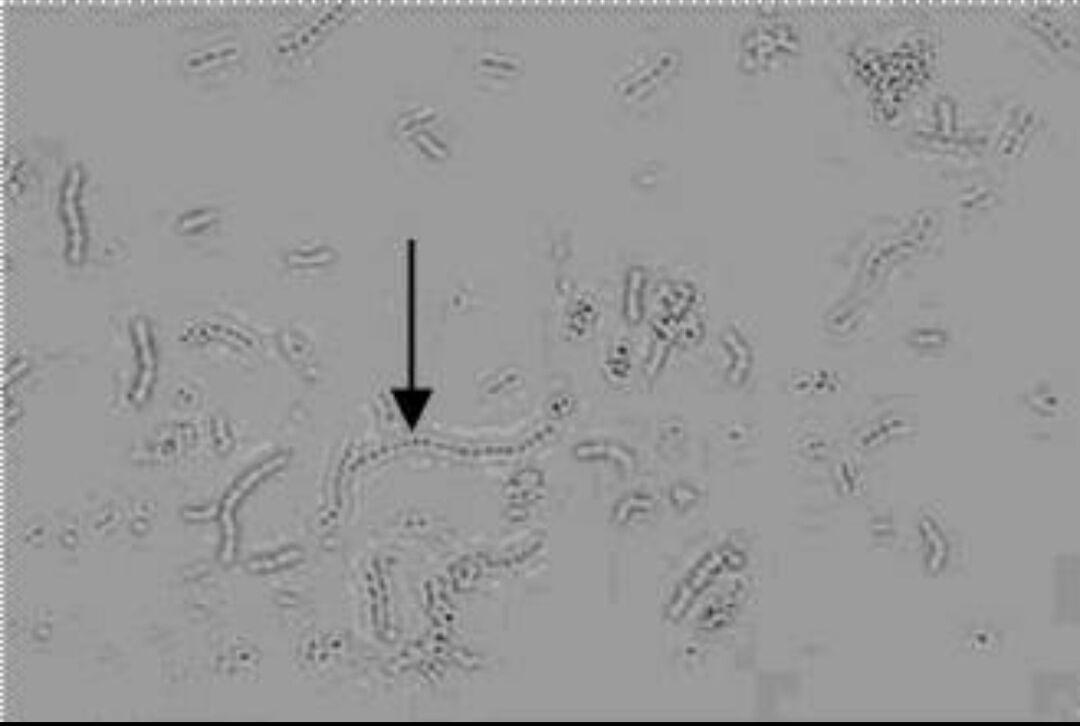

9.箭头所指目标:细菌

10、箭头所指细胞内结构的名称:细菌